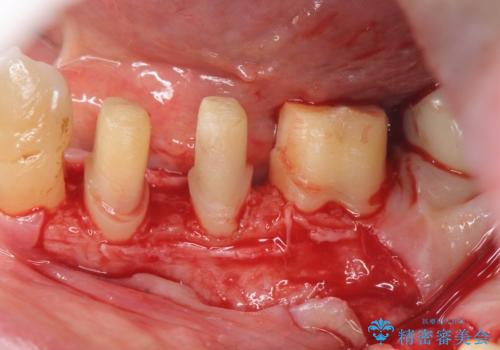

歯周病再生治療と歯周ポケット除去 歯周外科手術

- 他院で歯周病を指摘され、様子見ではなく根本的な治療はないか?とご相談に来院されました。

重度の歯周病で再生療法の適応ではない最後方臼歯は抜去行い、インプラント治療、

がたつきの強い天然歯を矯正治療で整えたのち、再生治療、歯周ポケットを除去する歯周外科手術を行いました。

再生療法を行ったことで、抜歯をされてもおかしくなかった歯を、残すことができました。